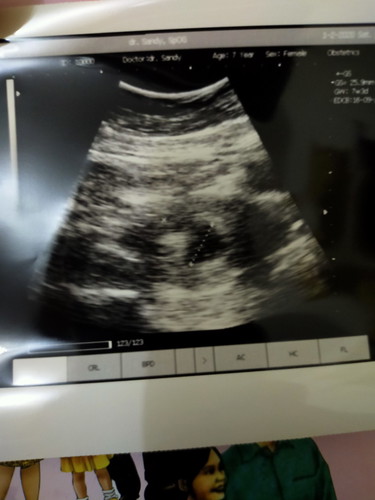

Usia 6w4d bru kliatan kantung kehamilan sj. Wajar gak yaaa

Wajar, bu. Bahkan ada yg baru penebalan dinding rahim